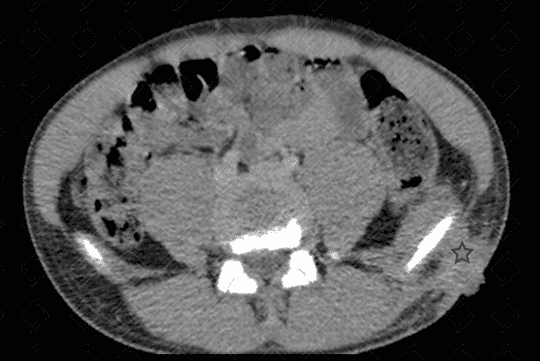

Texto alternativo para a imagem Figuras 1, 2 e 3. Créditos: Dra. Elazir Mota - Rio de Janeiro/RJ

Descrição das figuras 1, 2 e 3: Tomografia computadorizada de bacia, após a administração do contraste venoso. Paciente do sexo masculino, 13 anos, evidenciando extensa área de esclerose na asa do ilíaco esquerdo, com áreas líticas de permeio (setas vermelhas). Na janela de partes moles, observa-se aumento de partes moles e coleção adjacente à lesão óssea descrita (asterisco).